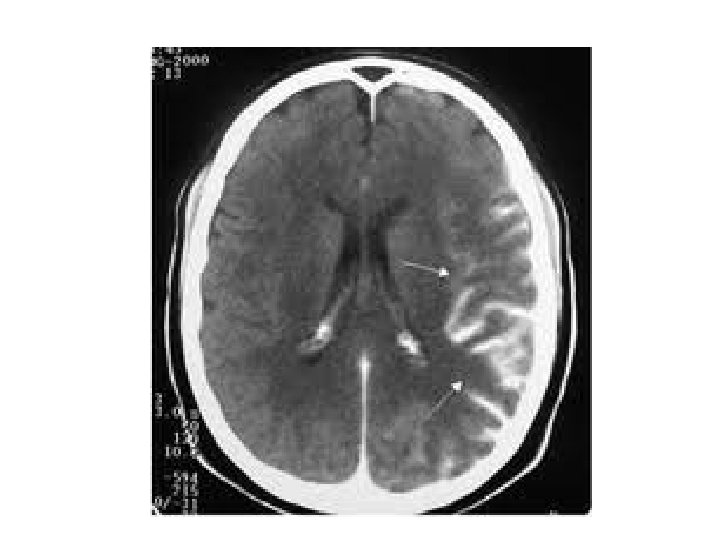

Signo de la ACM hiperdensa (signo de la cuerda)

Caso 2 2 - Ante estos hallazgos ¿cuál crees que es el diagnóstico más probable? AIT. B. IAM. C. Ictus isquémico agudo. D. Ninguna de las anteriores. A. Respuesta C: El TAC en las primeras horas después de un ictus isquémico puede ser normal. Es posible visualizar signos indirectos de isquemia cerebral: borramiento de surcos corticales, atenuación del núcleo lenticular, pérdida de diferenciación entre sustancia blanca y gris…